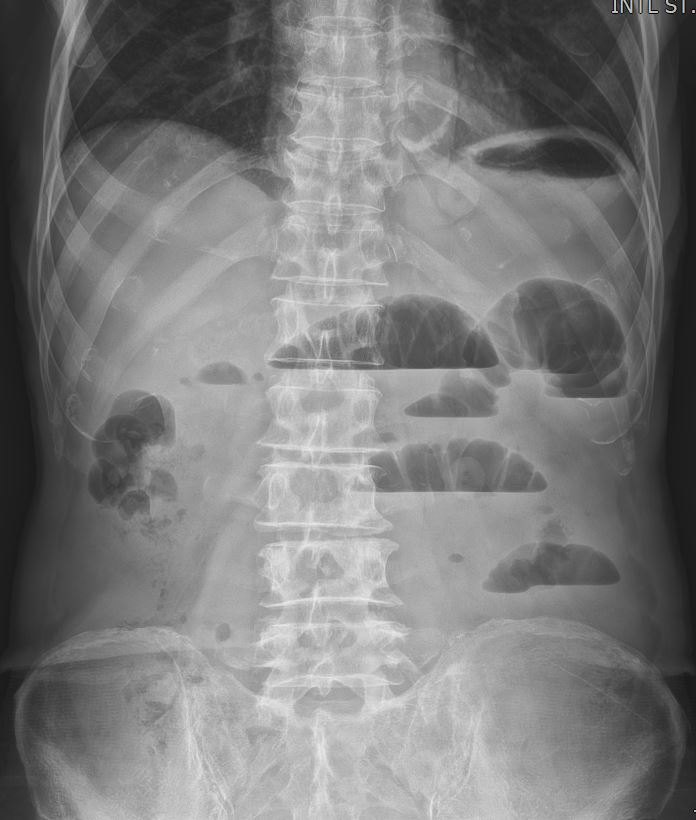

AXR: Step-ladder sign

임상양상상 장폐색을 시사하는 소견이 확인되며 AXR상 step-ladder sign이 있으므로 소장 폐색으로 진단한다.

• AXR상 step-ladder sign이 확인되므로 소장 폐쇄의 가능성이 매우 높고, CT상에서도 small bowel dilatation과 서로 다른 air-fluid level이 확인된다. 따라서 소장 폐색으로 진단한다.